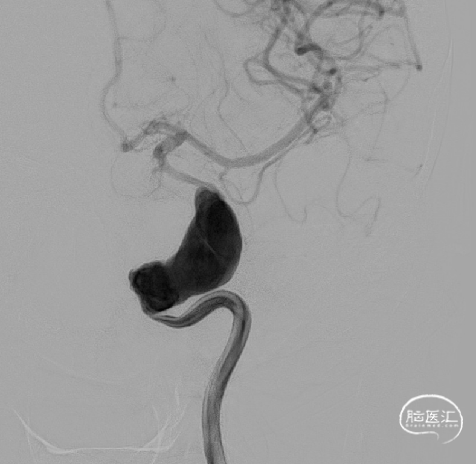

左颈内动脉巨大动脉瘤,动脉瘤大小31*14mm。

左颈内动脉造影。

左颈内动脉3D。